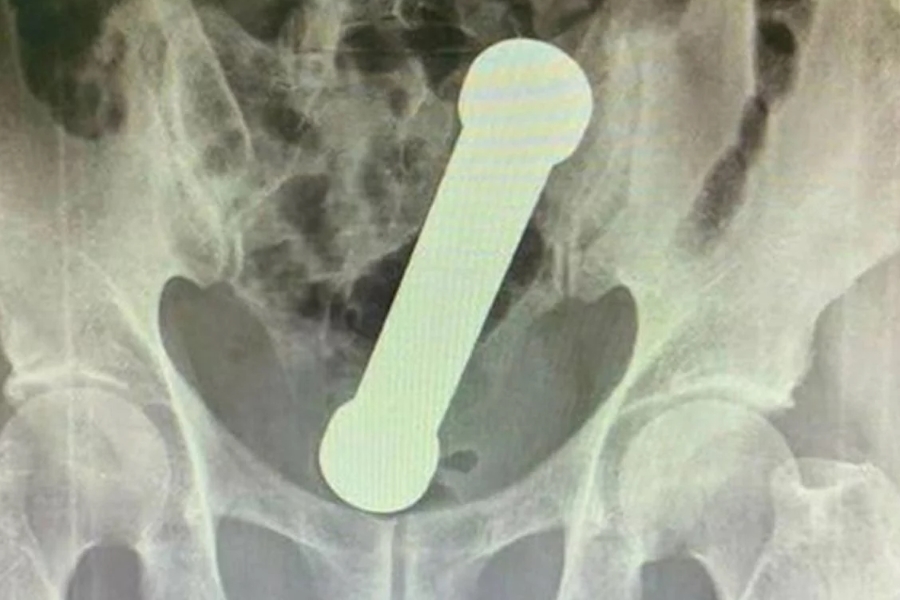

| Haltere de 2kg dentro do homem | Foto: Reprodução / Artigo Surgery Case Reports |

Segundo a equipe médica, o homem deu entrada no hospital com dores abdominais e com dificuldade de evacuar. Foi realizado radiografias e os médicos constataram que havia um objeto estranho. Ao examinar as imagens foi identificado um haltere de dois quilos dentro do paciente.

O homem foi levado ao centro cirúrgico, onde os médicos retiram o objeto de cerca de 20 centímetros sem a ajuda de pinça ou instrumentos.